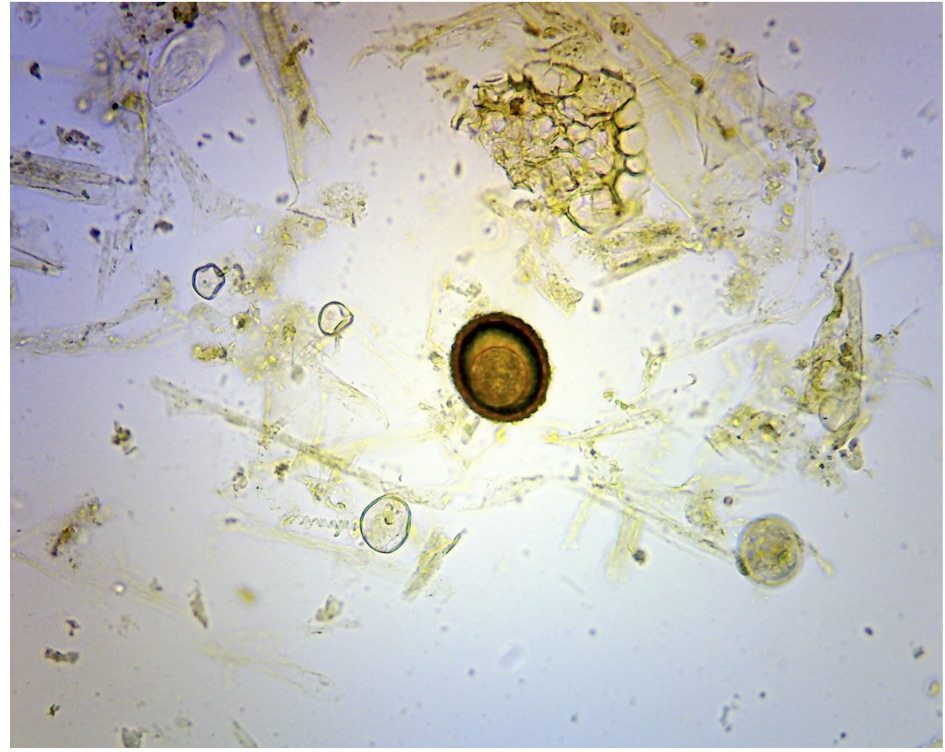

In order to make this decision process more transparent we have implemented a “worming package”, in which the diagrams below form the basis of our treatment protocol.

This package includes us assessing your specific horses risk in its given population. We will use the diagrams below to select which animals need treatment, which need monitoring and coupled with advice on pasture management we hope to keep worm burdens to an acceptable level.

Careful consideration should always be made when choosing when and how to worm horses. Using the flow diagram below you should be able to put your horse into one of three categories. Low / Medium and High risk.

(FEC = Feacal Egg Count / Worm Count)